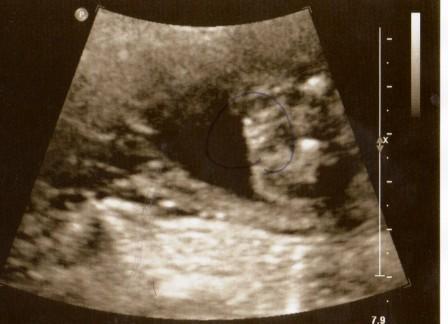

hatte gestern feindiagnostik und uns wurde ein mädchen prophezeit... hab sogar ein bild auf dem ich es eigentlich "eindeutig" finde,aber mein freund meint es könnte doch noch ein junge sein!wir haben schon ein mädchen und hatten auf einen kleinen stammhalter gehofft!aber nun freue ich mich auf noch eine kleine prinzessin!hauptsache gesund!! und nun: wie eindeutig empfindet ihr das bild?

Also ich habe es jetzt von allen Seiten her betrachtet, aber da kann ich weder Mädchen noch Jungen erkennen.... hmmmm.... kann echt nicht sagen, was man da sehen sollte!

Ähhh, liegt das Baby mit Beinen links und rechts gespreizt??? Dann würde ich auch sagen Mädel, aber ich bin eigentlich eine NULL im Ultraschall- Bild- erkennen...

ja die beine müssten links sein und das eine "vorderansicht"

... seh ich da Schamlippen

Auch ganz eindeutig für mich. Ein Mädel!

die Schamlippen sind sehr gut zu erkennen.Such dir im Internet Vergleichsbilder,zb bei youtube gibts auch so einige vergleichsmöglichkeiten. herzlichen glückwunsch

Ich sehe auch eindeutig ein Mädchen

aber sowas von eindeutig. Jetzt kannst Du beruhigt rosa Sachen kaufen gehen :)

Also wirklich was erkennen kann ich da auch nix, aber da nix hängt würd ich auch sagen Mädel. Unser Outingbild sieht so aus, da kann die Kleine nix leugnen ;)

Ich hab mir erst das Bild angesehen und dann den Text gelesen, eindeutig zwei Schamlippen :) Jungs sehen anders aus... und ich hab zwei davon :)